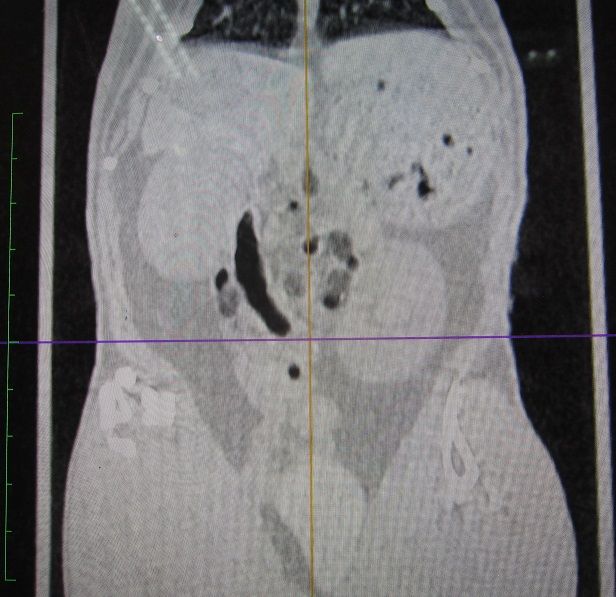

途中経過をCTで

まだまだたくさん残ってますが、👆これが👇こうなります。

完全に取り切れてない部分もありますが、すでに時間もかなりかかっていたのでひとまず終了。